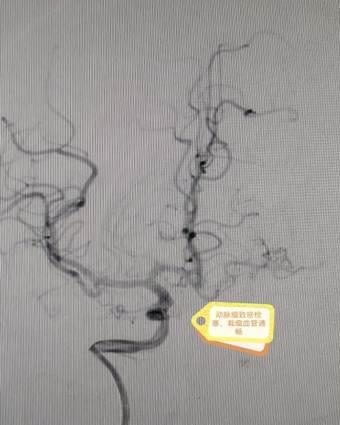

患者李阿姨3年前确诊左侧颈内动脉起始部闭塞,伴有左侧大脑中动脉M1段烟雾状改变及右侧颈内动脉眼段动脉瘤。由于病情稳定,无明显症状,未达到手术指征,初期采取密切随访观察。202512日,李阿姨前来复查时DSA显示右侧眼段动脉瘤增大,诊断为“烟雾病综合征、左侧颈内动脉闭塞、右侧眼段动脉瘤”。面对颅内外血管多发病变与动脉瘤进展的双重威胁,手术难度与风险极高,家属一度陷入焦虑。

术前DSA结果